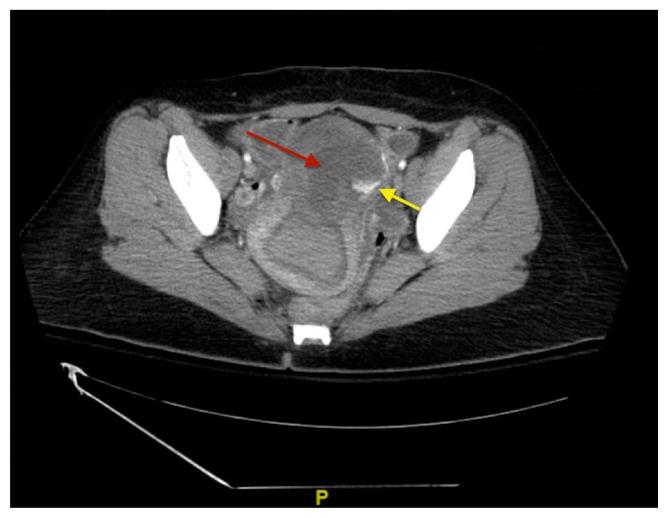

Uterine perforation is a rare but potentially life-threatening complication of gynecologic procedures. Serious complications include hemorrhage, infection, and injury to surrounding organ systems (eg, gastrointestinal, urological, vascular, etc.). Risk factors include advanced maternal age, prior gynecologic surgeries, and other anatomical features that impact the difficulty of accessing the uterine cavity. In this case report, we discuss a patient who presented to the emergency department (ED) with diffuse abdominal pain and vaginal bleeding that occurred after an elective dilation and curettage (D&C) for a termination of pregnancy. The diagnosis was suspected clinically and confirmed by imaging including ultrasound (US) and computed tomography (CT) of the abdomen and pelvis. The patient was managed operatively with a multidisciplinary approach including Gynecology, General Surgery, and Urology. The patient was stabilized and eventually discharged. Uterine perforation should be included in the differential for patients with a history of recent gynecologic instrumentation presenting with abdominal pain and vaginal bleeding. The stabilization of these patients requires aggressive volume resuscitation, controlling the source of bleeding, and emergent surgical consultation.

子宫穿孔是妇科手术中一种罕见但可能危及生命的并发症。严重并发症包括出血、感染以及对周围器官系统(如胃肠道、泌尿系统、血管等)的损伤。危险因素包括产妇年龄较大、既往妇科手术史以及其他影响进入子宫腔难度的解剖特征。在本病例报告中,我们讨论了一名患者,该患者因选择性刮宫术(D&C)终止妊娠后出现弥漫性腹痛和阴道出血而就诊于急诊科(ED)。临床怀疑诊断并通过包括腹部和盆腔超声(US)及计算机断层扫描(CT)在内的影像学检查得以证实。该患者通过包括妇科、普通外科和泌尿外科的多学科方法进行手术治疗。患者病情稳定,最终出院。对于近期有妇科器械操作史且出现腹痛和阴道出血的患者,鉴别诊断应包括子宫穿孔。这些患者的病情稳定需要积极的容量复苏、控制出血来源并紧急进行外科会诊。